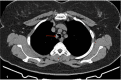

We report a rare case of a 57-year-old female patient with intraluminal tracheal obstruction caused by a benign schwannoma. She underwent successful bronchoscopic resection under general anesthesia, with no complications observed during the post-procedure follow-up. Tracheal schwannomas are exceedingly uncommon, and while conventional treatment involves surgical resection, bronchoscopic techniques, such as laser ablation, can be a valuable alternative, particularly for high-risk patients. Further studies are needed to explore the full potential of bronchoscopic interventions in managing tracheal schwannomas.